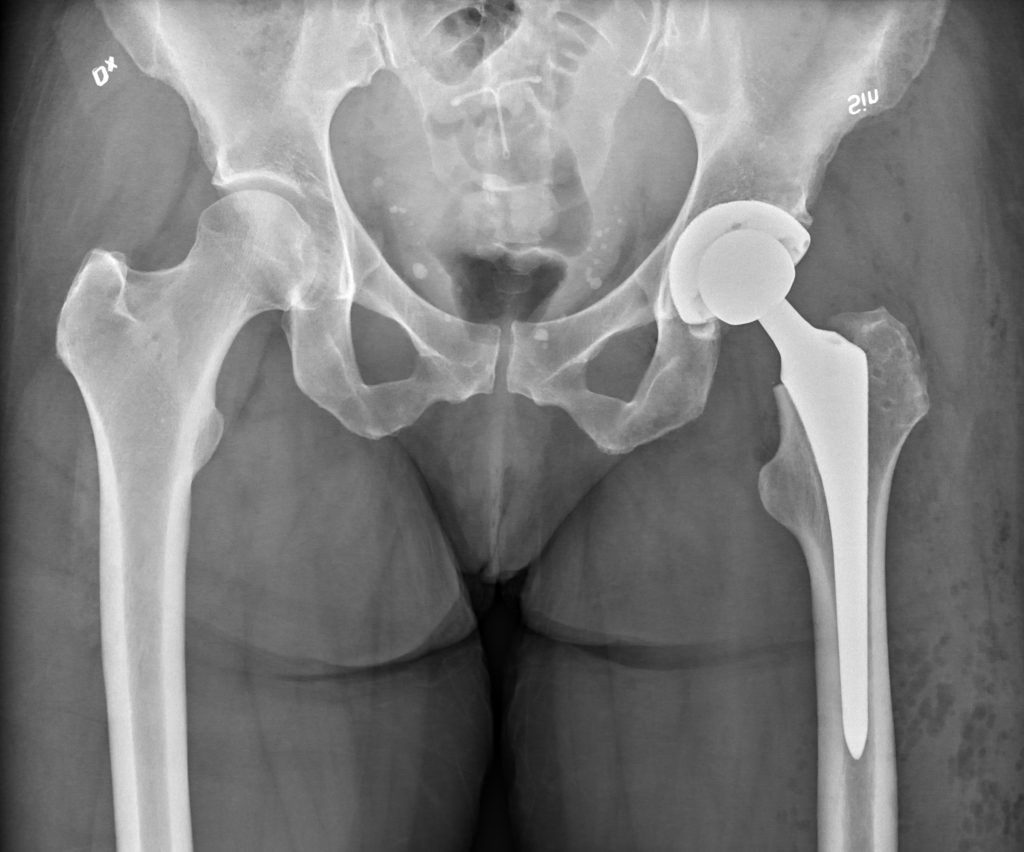

X-rays play a crucial role in planning hip replacement surgery, as they provide detailed information about the anatomy of the hip joint, the extent of damage, and the alignment of the bones. This information is essential for surgeons to determine the best surgical approach, select the appropriate implant size and position, and anticipate any potential challenges during the procedure.

- Preoperative Planning: X-rays allow surgeons to carefully assess the condition of the hip joint, including the severity of arthritis, the presence of bone spurs or deformities, and the alignment of the hip bones. This information helps them plan the surgical approach, whether it will be a traditional open surgery or a minimally invasive technique.

- Implant Selection: X-rays provide precise measurements of the hip joint, which are necessary for selecting the appropriate size and type of implant. The surgeon can determine the size and shape of the artificial joint components that will best fit the patient’s anatomy and restore proper joint function.

- Surgical Precision: X-rays during surgery can help guide the surgeon in real-time, ensuring accurate placement of the implants and minimizing the risk of complications. They can also be used to check the alignment and stability of the new joint after it has been implanted.

- Postoperative Monitoring: Serial X-rays taken after surgery can be used to monitor the healing process and assess the long-term success of the hip replacement. They can reveal any signs of loosening, infection, or other complications that may require further intervention.

In conclusion, X-rays are an indispensable tool in planning and performing hip replacement surgery. They provide surgeons with vital information about the hip joint, enabling them to make informed decisions, select the appropriate implants, and ensure the best possible outcome for their patients.